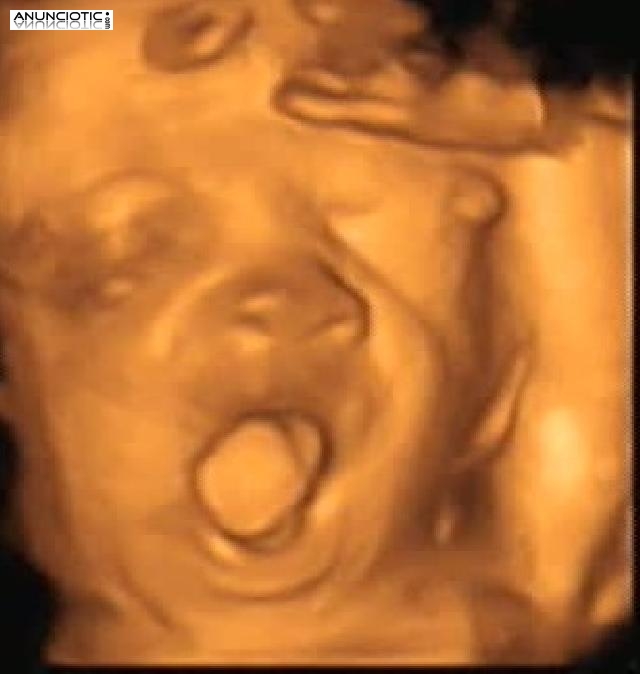

Ecomamá es un centro de imagen 4d prenatal cuyo objetivo es dar a conocer al bebé antes de su nacimiento. Esta maravillosa experiencia permite adentrarnos al pequeño mundo en el que vive el bebé. Gracias a ello se pueden ver gestos faciales nunca vistos como el bostezo, una sonrisa, el parpadeo o la succión. Todo ello en un ambiente cálido relajado y con todas las comodidades.

Un regalo para tu bebé a través de nuestra tecnología 4d prenatal.

¡Detén sus momentos inolvidables!